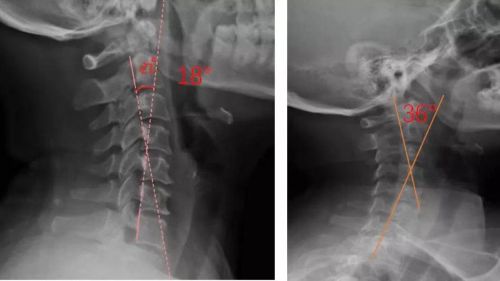

我們通過對頸部進行光學掃描與頸椎側位X光檢查,測量頸椎曲度,由專業矯形器師結合患者的情況設計個性化頸椎枕,部分或全部3D打印工藝制作完成,矯正頸椎的生理曲度。患者適配后拍攝X光片,做到精準矯正與治療,避免使用不適和矯枉過正。

患者適配前后側位X光,佩戴前18°,適配后36°